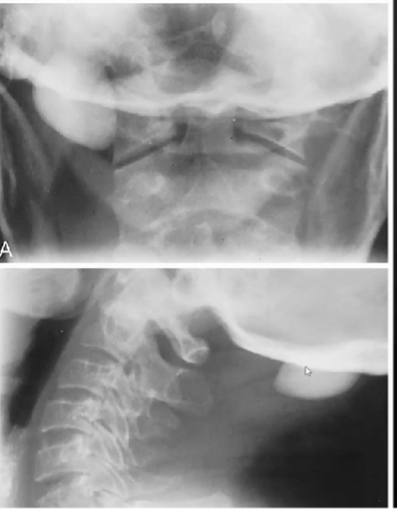

Ostéoblastome : Bénin

- Peut être partout, rare 1% des tumeurs primaires (bénin)

- Moins sévère que l’ostéome ostéoide en douleur

- Expansible, et maj son radiotransparante (parfois sclérotique

Ostéome ostéoïde :

- Dlr sévère, pire la nuit, dim +++ par l’aspirine

- Lésion lytique contour « flame shaped reactive sclérosis »

- fémur et tibia +++

- On le voit sur la scintigraphie (lésion active)

- Classique dans un pédicule

- H>F, 10-25 ans.